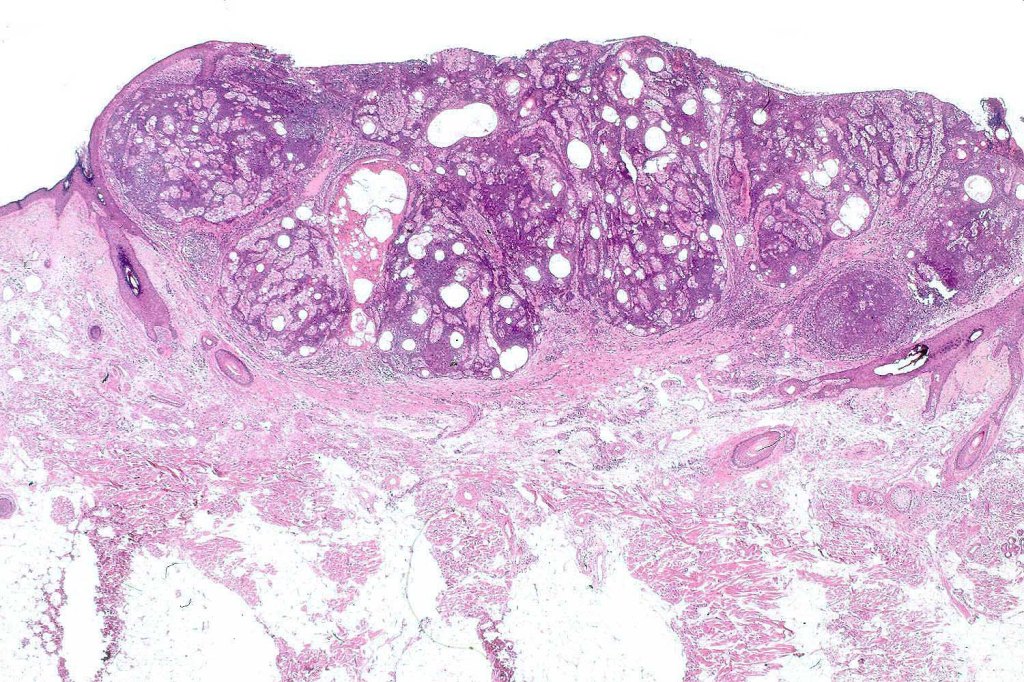

Histological features

•Variable continuity with epidermis

•Multinodular with surrounding collagenous stroma

•Random distribution of basaloid cells & sebocytes (<50% sebocytes)

•Duct formation, often with holocrine secretion generally present

•Mitoses sparse to conspicuous

•Absent peripheral palisading & retraction artifact

•Cystic variant

•Subtypes include rippled pattern, carcinoid-like & reticulated